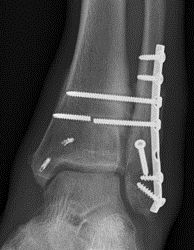

Unstable Weber B / torn deltoid ligament

Bimalleolar equivalent

Management

ORIF fibular

- ensure medial joint space fully reduced

- may need to open medial joint / removed osteochondral fragments / deltoid ligament

ORIF options

Plate - 1/3 tubular / DCP / anatomic locking plate

Fibular nail

ORIF